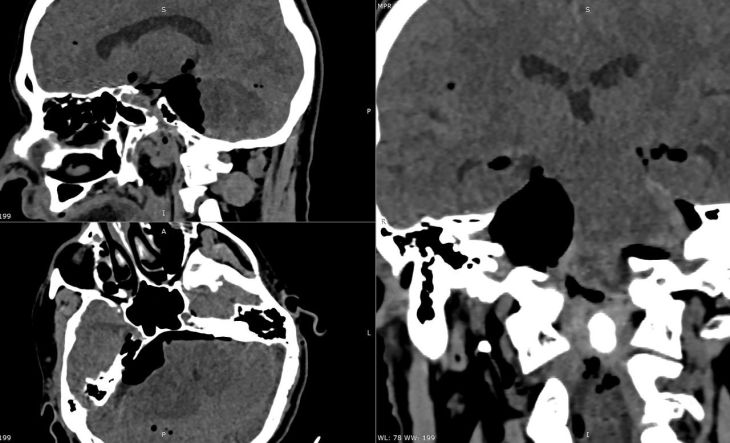

«В наш центр пациент поступил с жалобами на прогрессирующую одностороннюю тугоухость, постоянный шум в правом ухе, нарастающую неустойчивость при ходьбе и снижение чувствительности в области лица. На МРТ головного мозга визуализировалась гигантская вестибулярная шваннома — доброкачественная, но крайне опасная опухоль, которая развивается из черепных нервов», — сообщил нейрохирург центра ФМБА Андрей Ситников.

По словам специалиста, опухоль размером с орех уже сдавливала ствол мозга — центр дыхания и сознания, кроме того, возникал риск смертельно опасного повышения давления в черепе, сохранялась угроза необратимого паралича лицевого нерва уже страдали функции глотания и речи.